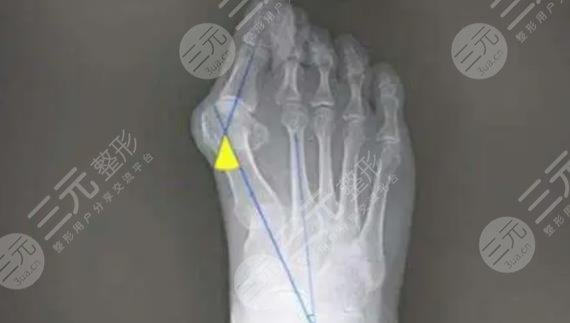

大腳骨外翻是比較常見(jiàn)的一種足部疾病,主要的表現(xiàn)就是會(huì)出現(xiàn)大腳趾向外翻的問(wèn)題,還是較為明X的,通?;颊哌€會(huì)出現(xiàn)大腳趾內(nèi)側(cè)骨性突起。這種疾病不僅影響美觀,也會(huì)帶來(lái)足部的不適癥狀,如果不及時(shí)緩解就會(huì)越來(lái)越嚴(yán)重,較終會(huì)影響到正常的站立和行走,所以需要早診斷早緩解。

緩解大腳骨外翻的方式比較多,具體選擇哪一種方法需要根據(jù)每個(gè)人的病情去評(píng)估。在選擇方式之前,要根據(jù)患者的癥狀,通過(guò)身體的檢查和X線來(lái)綜合去判斷,不可以盲目的去選擇,因此一定要到正規(guī)的醫(yī)院,請(qǐng)經(jīng)驗(yàn)豐富的醫(yī)生去幫助選擇和緩解。在緩解之后也要定期進(jìn)行康復(fù)訓(xùn)練,避免一些不良反應(yīng)出現(xiàn)。